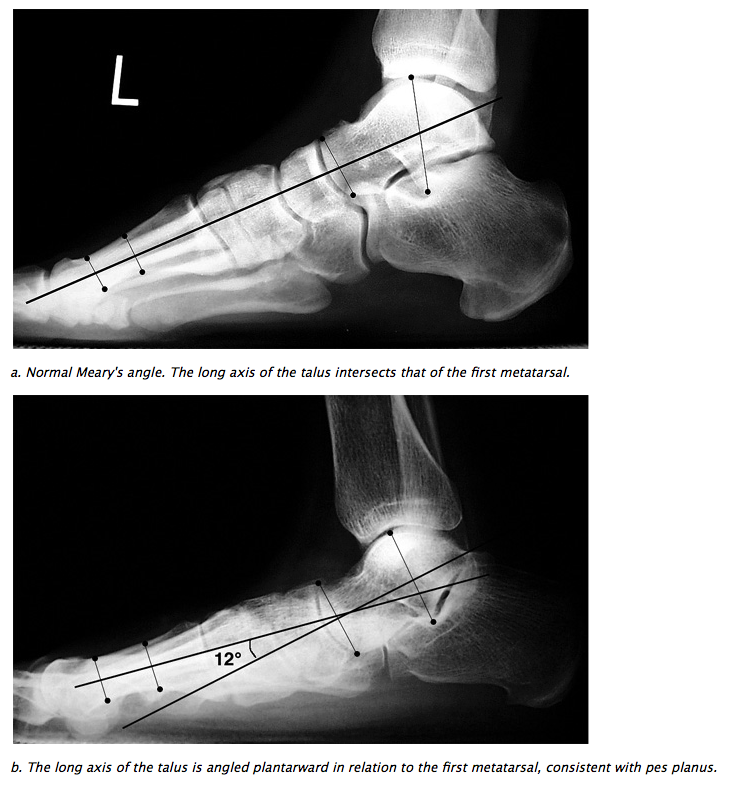

COLLAPSE OF LONGITUDINAL ARCH

• Lateral: 1st metatarsal talar angle